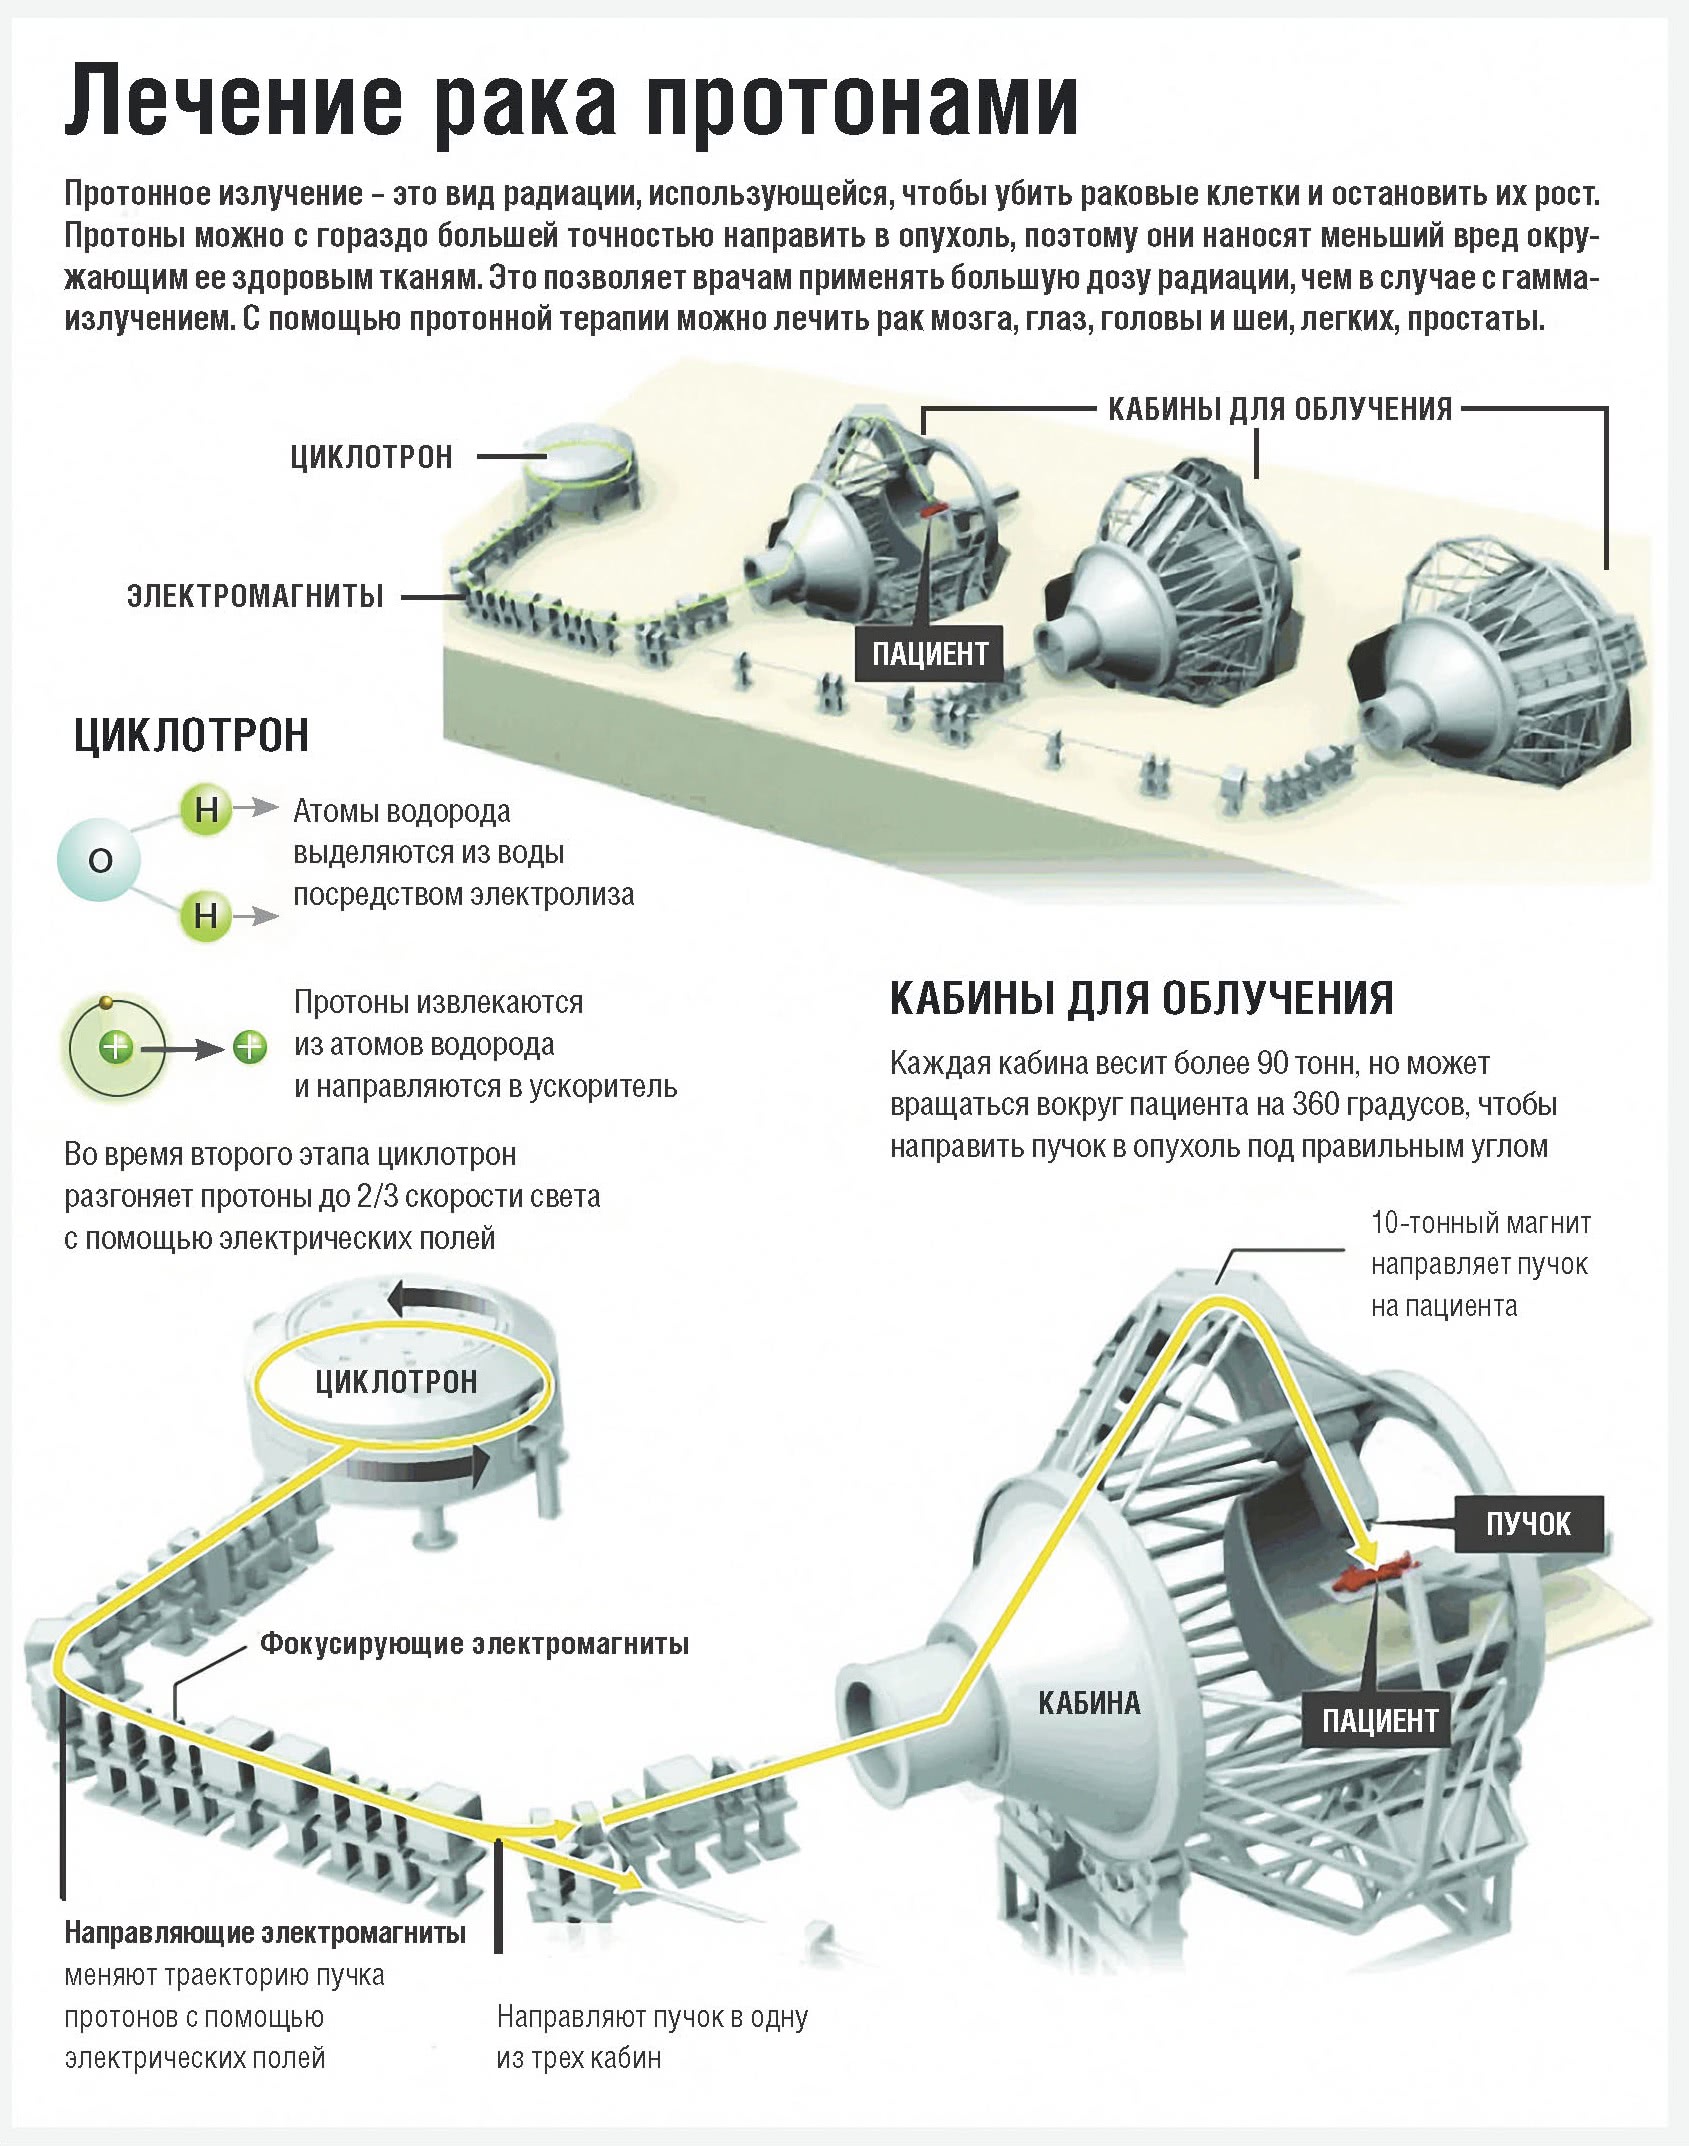

И вдруг дело сдвинулось с мертвой точки. Первый государственный клинический центр протонной терапии, входящий в структуру Федерального высокотехнологичного центра медицинской радиологии должен начать работу уже через два года в Димитровграде Ульяновской области. Ускоритель протонов С-235 для центра рассчитали, собрали и настроили физики Объединенного института ядерных исследований. Произвела детали всемирно известная бельгийская компания IBA (Ion Beam Applications), построившая 11 центров протонной терапии по всему миру и строящая еще 12 таких же. Она же сертифицировала совместную российско-бельгийскую машину для лечения людей.

– Мы лечим 100-120 пациентов в год, – детализирует главный инженер ОИЯИ, член-корресподент РАН Григорий Ширков. – Чтобы обеспечить стоимость лечения в 20 тысяч долларов, должен быть большой поток пациентов. Это технологически очень сложная задача. Должна быть не одна медицинская кабина, как у нас, а три-четыре. Мы должны уметь очень быстро переключать пучок из одной кабины в другую. Потому что пациент облучается около двух минут, а 20 минут его готовят: проверяют его положение, правильно ли будет подведена доза и так далее. Желательно снизить время подготовки. В Димитровграде оно будет уже меньше. Там в проект заложена система предварительного позиционирования пациента, куда включены специальные магниторезонансные и компьютерные томографы, которые предназначены не для диагностики, а именно для правильного позиционирования. То есть положение пациента определяют под томографом, а не под пучком. После этого дека с зафиксированным пациентом переезжает по специальным рельсам в кабину для облучения. Такие томографы стоят несколько миллионов долларов. Это делает процедуру дороже, но увеличивает пропускную способность центра на 20-30 процентов за счет сокращения времени подготовки. Томографы в системе предварительного позиционирования окупаются за год. Димитровград – это третий в мире центр, оснащенный подобным оборудованием. Такие же сейчас строятся в Эссене и Праге.

Дело, оказывается, вот в чем. Установки для фотонной лучевой терапии на базе электронных ускорителей и кобальтовых источников, которые облучают опухоли рентгеновскими или гамма-лучами, есть практически в каждом областном онкодиспансере. Но в силу особенностей облучения фотонами они отдают свою энергию не только больным клеткам, но и здоровым тканям, через которые проходят по пути к опухоли. Современная стереотаксическая (от греч. stereos – объемный, пространственный и taxis – расположение; стереотаксис – трехмерная локализация цели) фотонная терапия умеет фокусировать максимальную дозу облучения в опухоли и поэтому минимально воздействует на здоровые ткани. На опухоль нацеливаются с разных направлений одновременно более десятка пучков рентгеновских или гамма-лучей, так что здоровые ткани получают безопасные для них дозы, а в опухоли они суммируются. Такие установки существенно дешевле протонных ускорителей. Но область применения этого вида терапии – небольшие злокачественные очаги или малого размера метастазы.

Протонной терапии подвластны большие опухоли – объемом до 3 литров, а свойства протонов, как мы уже говорили, позволяют примерно в два раза меньше по сравнению с гамма-квантами облучать здоровые органы и ткани, которые пучку частиц приходится пройти насквозь по пути к очагу болезни. Эффективность протонной терапии выше фотонной примерно вдвое.